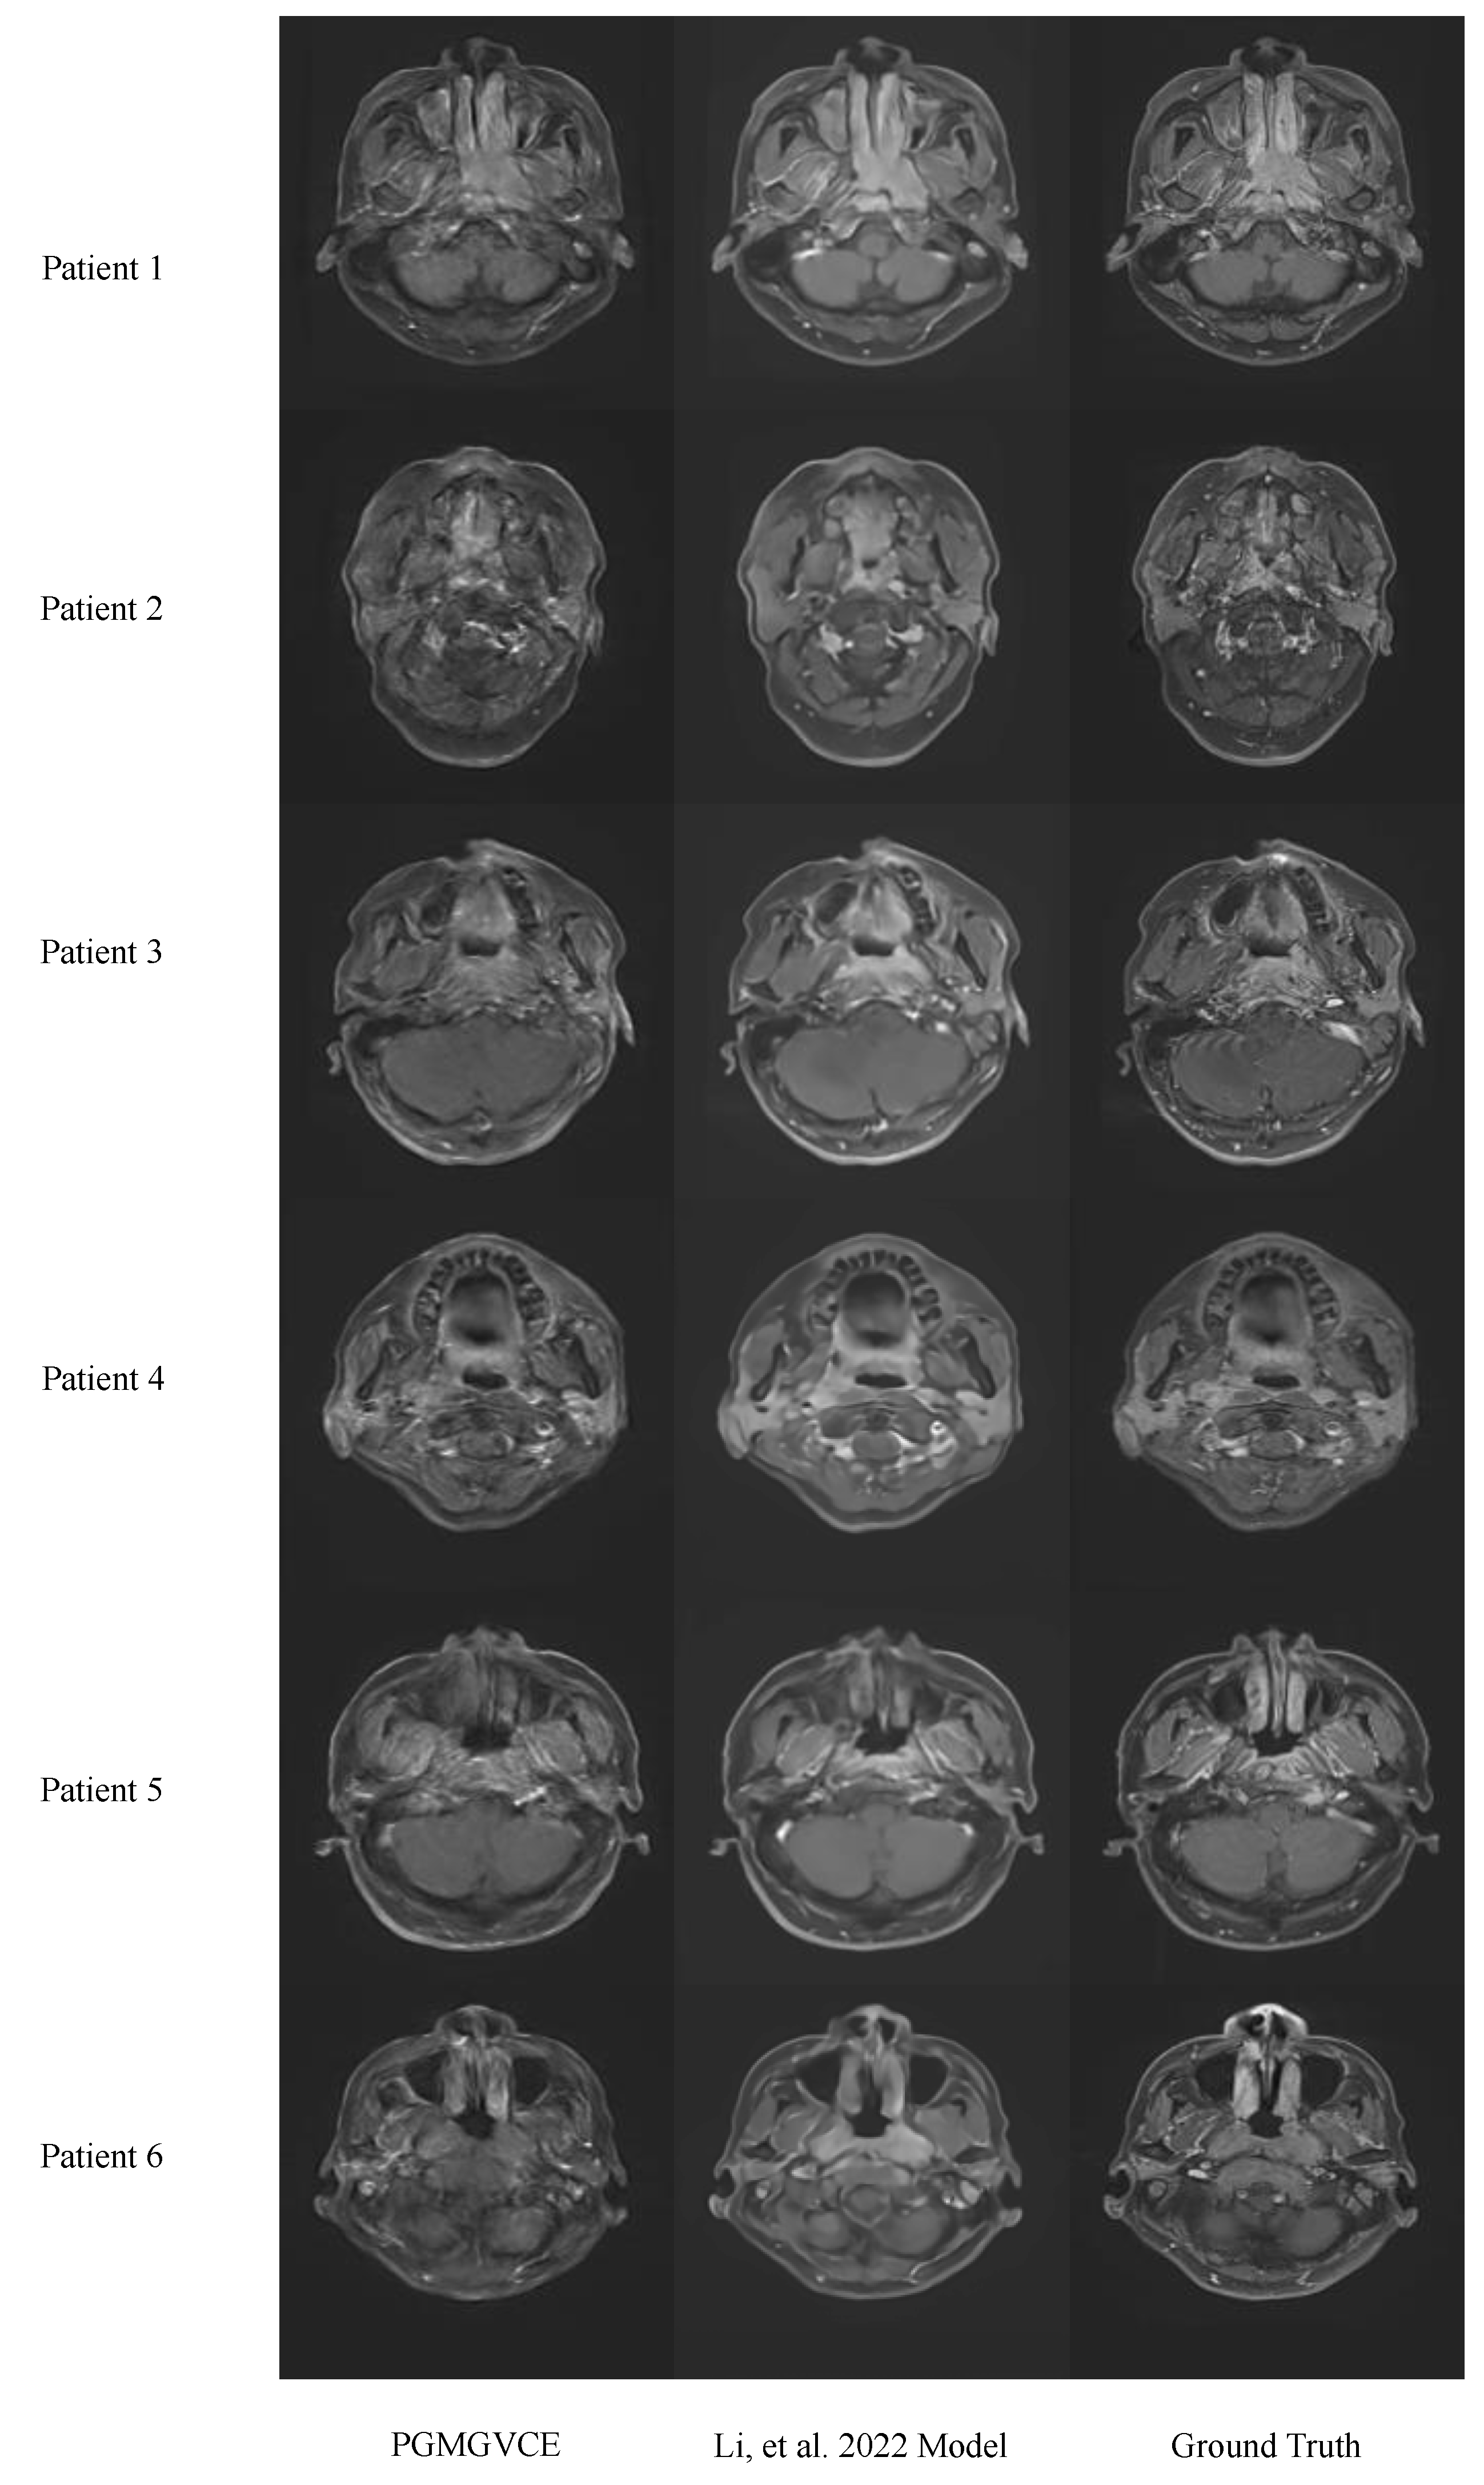

We compared the PGMGVCE with the model in (16) using MAE, MSE and SSIM (Table 1). The comparison statistics between the models and the ground truth are very close to each other. As shown in Figure 3, the VCE images qualitatively also look very similar. These indicate that, in terms of accuracy, the PGMGVCE is similar to that in [22]. However, qualitatively, the texture of the model in [22] appears to be smoother than the ground-truth T1C. This can be illustrated by the texture statistics. The PGMGVCE has a texture closer to the ground truth than the model in [22]. The TMSVPMI, TAVPMI, TFPMI and VFPMI of the ground-truth T1C, VCE images produced by the PGMGVCE and model in [22] are shown in Table 2. The p-values of TMSVPMI, TAVPMI, TFPMI and VFPMI of the model by [22] are the same as the ground-truth T1C, that is, 0.002, 0.003, 0.004 and 0.0001, respectively, which is statistically significant to claim that the TMSVPMI, TAVPMI, TFPMI and VFPMI of the PGMGVCE are larger than those of the model in [22]. This is an indication that the texture of the result of the PGMGVCE is closer to the realistic ones.

Figure 3. Results of the Pixelwise Gradient Model with GAN for Virtual Contrast Enhancement (PGMGVCE), the model in [22] and ground truth. It can be seen, qualitatively, that the texture of model in [22] appears to be smoother than the ground truth.